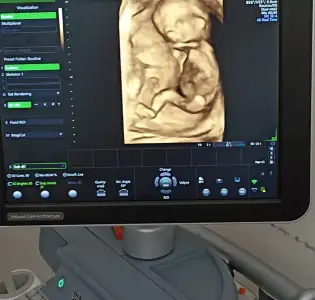

11+3 ten selamlar

Az önce doktorum aradı, fetal dna sonucum gelmiş. Herhangi bir anomali yokmuş. O kadar sevindim ve o kdar büyük bir yük kalktı ki omuzlarımdan inanılmaz

Fetal dna olunca cinsiyeti de söylemesini istedik; kız geliyooor

Hepimizin bebeği sağlıkla gelsin. İster kız ister erkek farketmiyordu bizim için. Çünkü ilk bebeğimiz ve 2 düşük sonrasında tüp bebekte tek embriyo elde etmiştik, onu gönderdik rahime ve tutunmuş. İnanılır gibi değil gerçekten. Havalara uçuyoruz şu anda evde